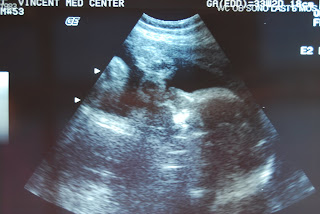

For the past two doc appointments, I have been measuring about two inches bigger in the belly than my gestional dates, so I was recently sent for an ultrasound to make sure we are on target and there are no other reasons for the big belly.

So, off to my ultrasound I happily went since I'd get to see the little (or big!) man again - I hadn't seen my babe since the 20 week mark. So it was nice to see him wiggling around and happy in there. I even caught a glimpse of him sucking his little thumb- ahhh! I can't wait for him to get here!!

The doc called the following Monday and said that everything looks within range on the ultrasound and all is fine. Apparently the huge head I saw on the ultrasound screen is normal? Faaaaaantastic! She also said that they guess he weighs about 4.5 lbs which makes me want to squeeze him! I can't wait until his sweet, big head is out in the world!